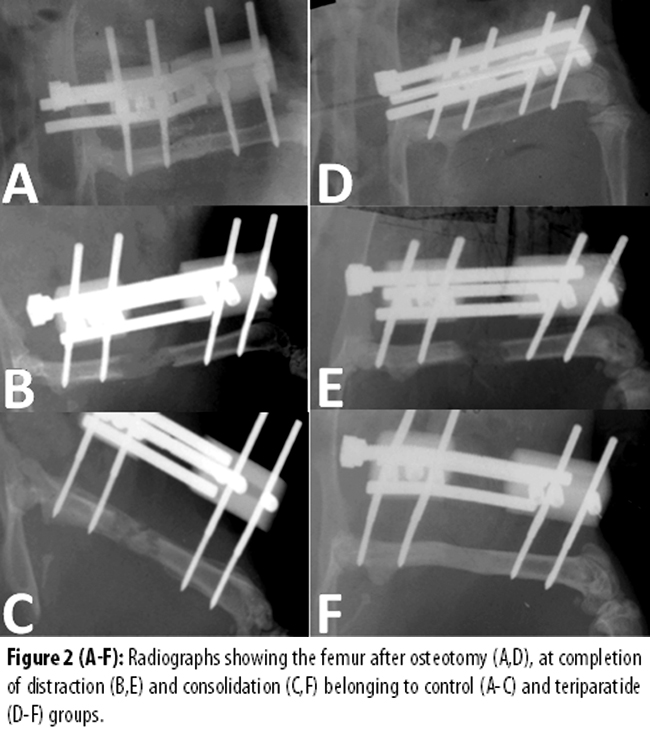

X-rays were performed at 3 time points; immediately after surgery, at the end of distraction, and at the end of another 4 weeks of consolidation phase. X-rays were scored for the quality of regenerated bone according to the method of Lane and Sandhu.7 Three blinded observers performed scoring of scanned X-ray images independently, and the mean was used for statistical comparisons using Mann-Whitney test.

In 2(33.3%) rats in the saline group, new bone formation was observed, while in all the 6(100%) rats in teriparatide group there was new bone formation Figure-2).

Mean radiological score was 2.2±0.5 for the saline group compared to 3.2±0.3 for teriparatide group, but the difference was not statistically significant (p>0.05).